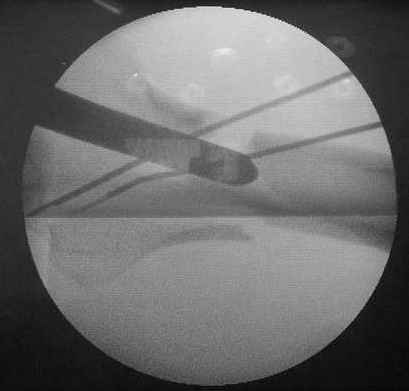

Пациенту М., 30-ти лет, 1,5 года назад в одной из московских больниц был выполнен остеосинтез бедренной кости штифтом UFN (диаметр штифта 9 мм).

К нам больной поступил с признаками ложного сустава бедренной кости, перелома

штифта и дистального блокирующего винта (images 1,2,3).

27 марта выполнено удаление блокирующих винтов (сломанный винт пришлось высверливать цапфен-бором), сломанного штифта (дистальный фрагмент удален через канал, образованный разверткой из коленного сустава - image 4),

рассверливание костно-мозгового канала, реостеосинтез штифтом UFN (при проведении штифта в дистальном отломке мы использовали поляризующий винт, диаметр штифта 10 мм). После операции в связи гемартрозом дважды (на 1 и 3 сутки) выполняли пункцию коленного сустава. Сейчас признаков скопления жидкости в полости сустава нет. Послеоперационные рентгенограммы - images 5, 6, 7.